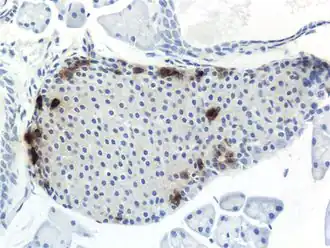

![]() Tinción inmunohistoquímica de polipéptido pancreático en páncreas de ratón | ||||